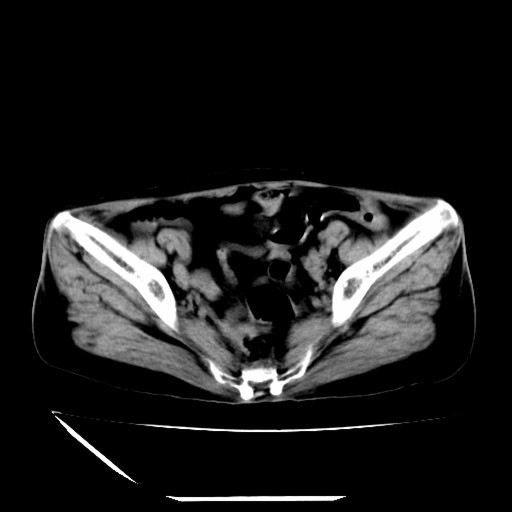

标题: CT16840:女-63岁,下腹部疼痛, [打印本页]

标题: CT16840:女-63岁,下腹部疼痛,

补充资料:血象是13.5,临床拟诊阑尾炎

本人诊断是右肾周围炎,阑尾炎,盆腔少许积液!

我觉得你的诊断欠妥;1)右肾周围炎症?是个什么诊断?2)明显的阑尾炎也没看到,最好不要这样写,就是道格拉斯窝内少量积液。

道格拉斯窝内少量积液。

支持 阑尾炎,盆腔少量积液。